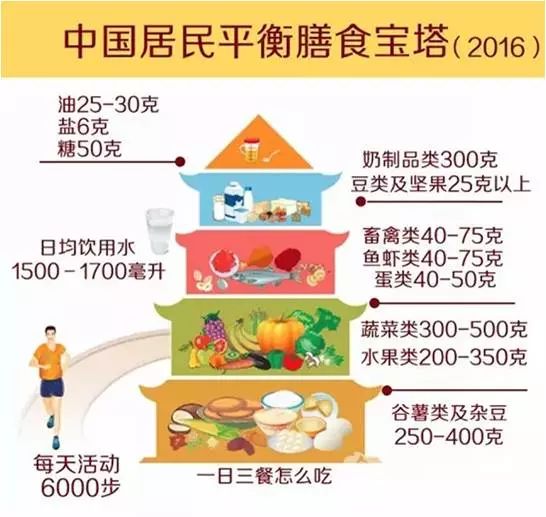

肺癌药物治疗期间的营养支持

肺癌药物治疗期间的营养支持

术后忌口太多,“发物”不敢吃,白细胞减少,免疫力下降...

术后忌口太多,“发物”不敢吃,白细胞减少,免疫力下降...

肺癌术后,应该怎么吃?——上海市胸科医院举办“胸科科普小讲堂”...

肺癌术后,应该怎么吃?——上海市胸科医院举办“胸科科普小讲堂”...